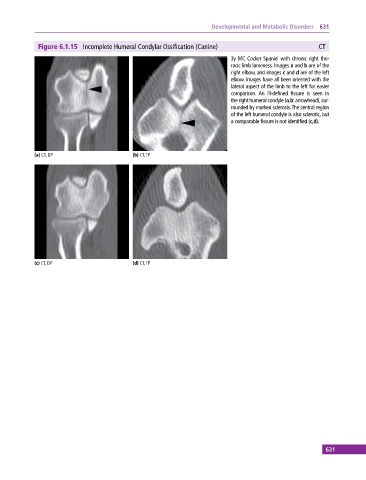

Figure 6.1.15 Incomplete Humeral Condylar Ossification (Canine) CT

3y MC Cocker Spaniel with chronic right tho

racic limb lameness. Images a and b are of the

right elbow, and images c and d are of the left

elbow. Images have all been oriented with the

lateral aspect of the limb to the left for easier

comparison. An ill‐defined fissure is seen in

the right humeral condyle (a,b: arrowhead), sur

rounded by marked sclerosis. The central region

of the left humeral condyle is also sclerotic, but

a comparable fissure is not identified (c,d).

(a) CT, DP (b) CT, TP

(c) CT, DP (d) CT, TP